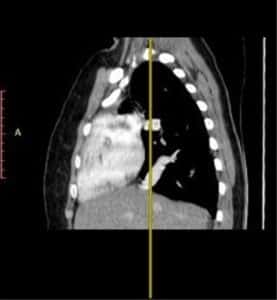

Investigations: Initial chest radiography revealed right lung volume loss and ipsilateral mediastinal displacement, raising suspicion for venous anomalies (Figure 1). A contrast-enhanced chest computed tomography (CT) scan was then performed, confirming the diagnosis of scimitar syndrome. The imaging demonstrated an anomalous right pulmonary vein draining into the IVC, associated with hypoplasia of the right lung (Figure 2, Figure 3, Figure 4). Additionally, two-dimensional transthoracic echocardiography was conducted to evaluate for any associated cardiac anomalies, which were not detected. An abdominal ultrasound was performed to assess liver size and anatomical relationships, yielding unremarkable results.

Figure 3: Chest CT

Sagittal view of the thorax showing a linear scimitar-shaped opacity.